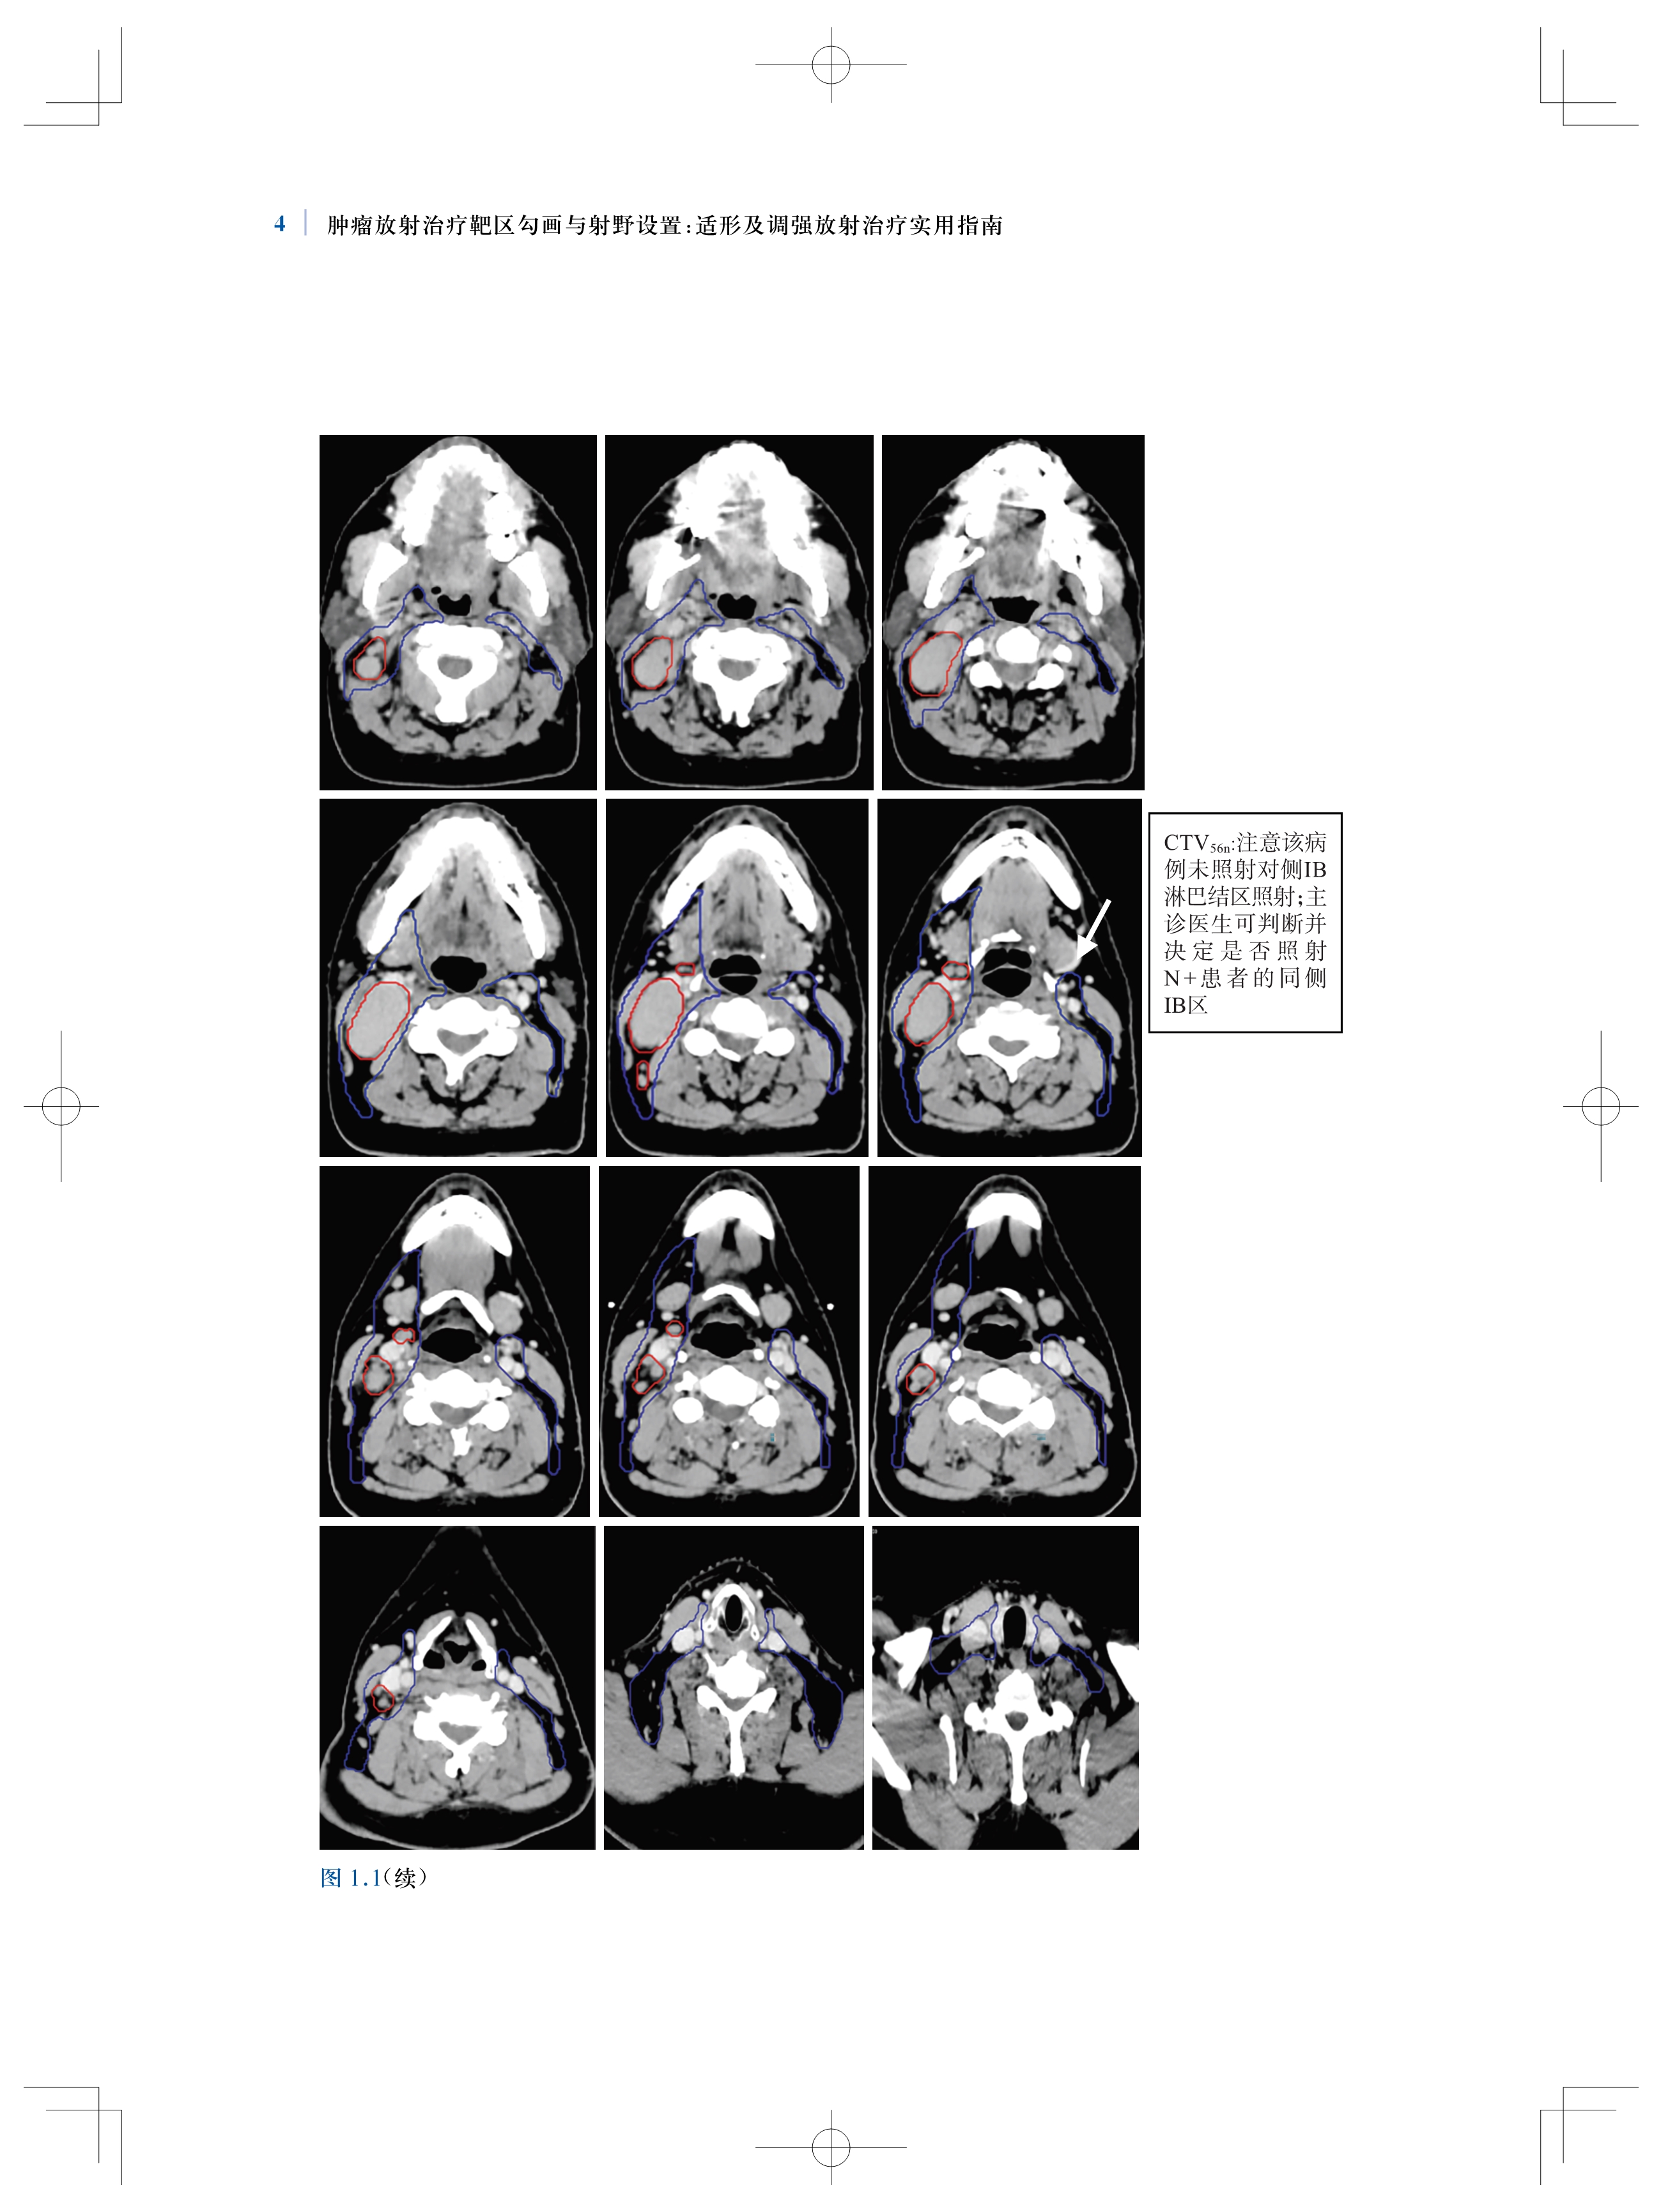

书名:肿瘤放射治疗靶区勾画与射野设置:适形及调强放射治疗实用指南(原著第2版)